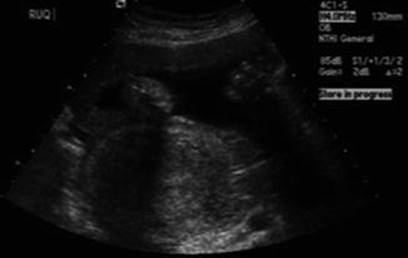

16.7.1 Transvaginal/Transabdominal Ultrasound

A transvaginal and transabdominal ultrasound should be performed to search direct and indirect findings of suspected uterine rupture. Direct signs are thinned wall with bulging of fetal parts (Fig. 16.6) or for visualization of the rupture. The fetus can be partly or completely out of the uterus (Fig. 16.7). Indirect signs are free peritoneal fluid (blood) especially in the pouch of Douglas, extraperitoneal hematoma, intrauterine blood, empty uterus, gestational sac above the uterus (Fig. 16.8), and large uterine mass with gas bubbles [183, 184, 207].

Fig. 16.7

Ultrasound image demonstrating contracted uterus (lower) with fetal extremities and amniotic sac outside the uterus [183]

Fig. 16.8

Ultrasound image demonstrating contracted uterus, endometrial stripe, and no intrauterine gestation, with the placental tissue above and bladder to the right [183]